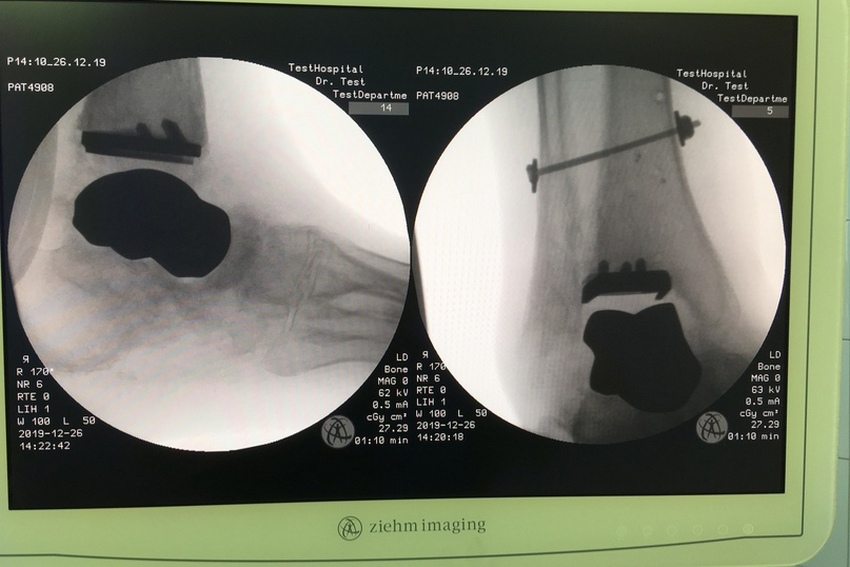

До операции. Фото: пресс-служба ННИИТО

После операции. Фото: пресс-служба ННИИТО